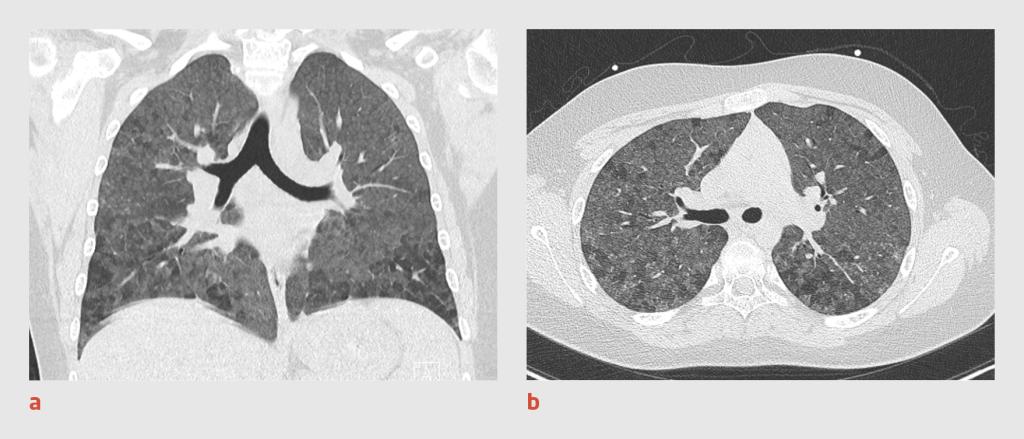

De uitslag van de PCR op nasofaryngeale uitstrijken voor het SARS-CoV-2-virus en andere respiratoire virussen (influenzavirus type A en B, humaan metapneumovirus, para-influenzavirus type 3, respiratoir syncytieel virus type A en B, Mycoplasma pneumoniae) was bij herhaling negatief. Vanwege een onveranderd klinisch beeld en de kans op een fout-negatieve PCR-uitslag werd een lagedosis-CT-scan van de thorax verricht. Deze toonde beiderzijds afwijkingen met een matglas-aspect en enkele kenmerken die niet overeenkwamen met het klassieke beeld van een covid-19-pneumonie bij volwassenen (zie figuur). De CO-RADS-score was 4, wat betekent dat de afwijkingen pasten bij covid-19 of andere infectie.2 De behandeling werd gecontinueerd. Patiënt bleef koortsvrij en herstelde langzaam. Na een opnameduur van 7 dagen kon hij ontslagen worden uit het ziekenhuis.

Blanco CT-scans van de thorax van een 12-jarige patiënt. (a) Op de coronale opname zijn beiderzijds afwijkingen met een matglas-aspect zichtbaar. De bovenste longvelden zijn vrijwel volledig aangedaan, de onderste longvelden in mindere mate. (b) Op de transversale opname is te zien dat deze afwijkingen zowel centraal als perifeer gelegen zijn en dat deze in contact komen met de pleura visceralis.